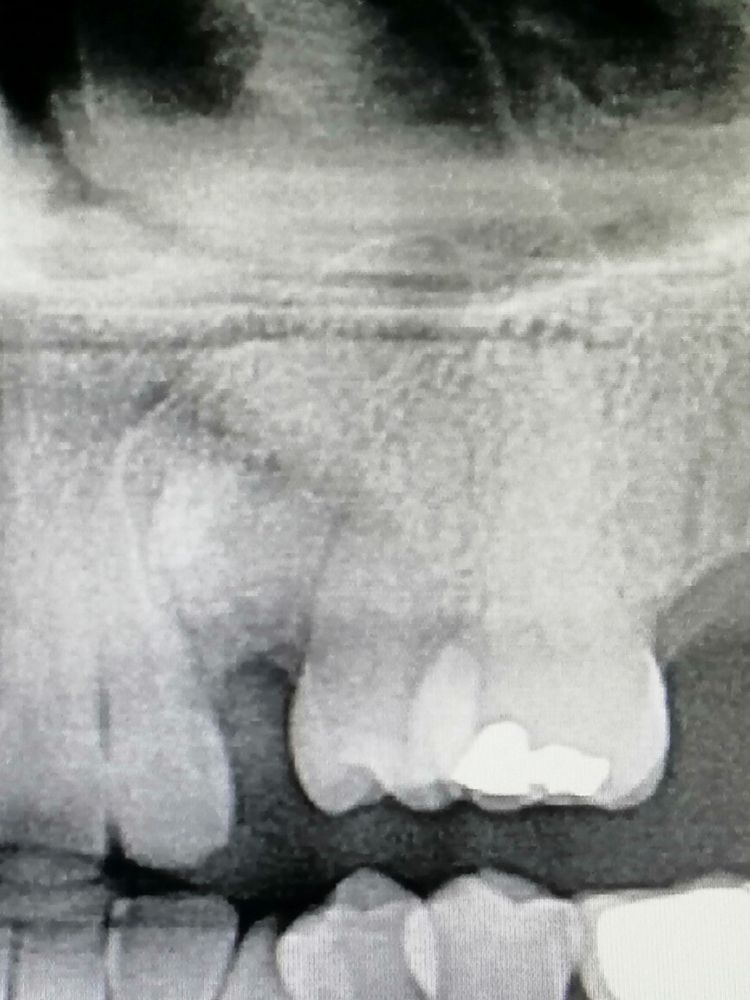

Tras una primera exploración con TAC dental, pudimos observar cómo se encontraba incluido en el hueso el canino superior izquierdo. Es un hecho muy frecuente que tratamos a menudo en nuestras clínicas, es asintomático para los pacientes y la solución suele ser también recurrente.

Al tener la pieza 2.4 fracturada, le propusimos al paciente la extracción de dicho premolar y la posterior colocación de un implante dental, con la peculiaridad de que presentaba un canino incluido que impediría la colocación del implante paralelo a las piezas contiguas.

En este caso, había que optar por otra solución. La propuesta de tratamiento en este caso fue la retirada de ambos dientes, el 2.3 (el canino incluido) y el 2.4 fracturado, regeneración con biomateriales y posterior colocación de una prótesis provisional hasta que los tiempos de cicatrización y regeneración ósea nos dieran la oportunidad de colocar el implante dental correspondiente.